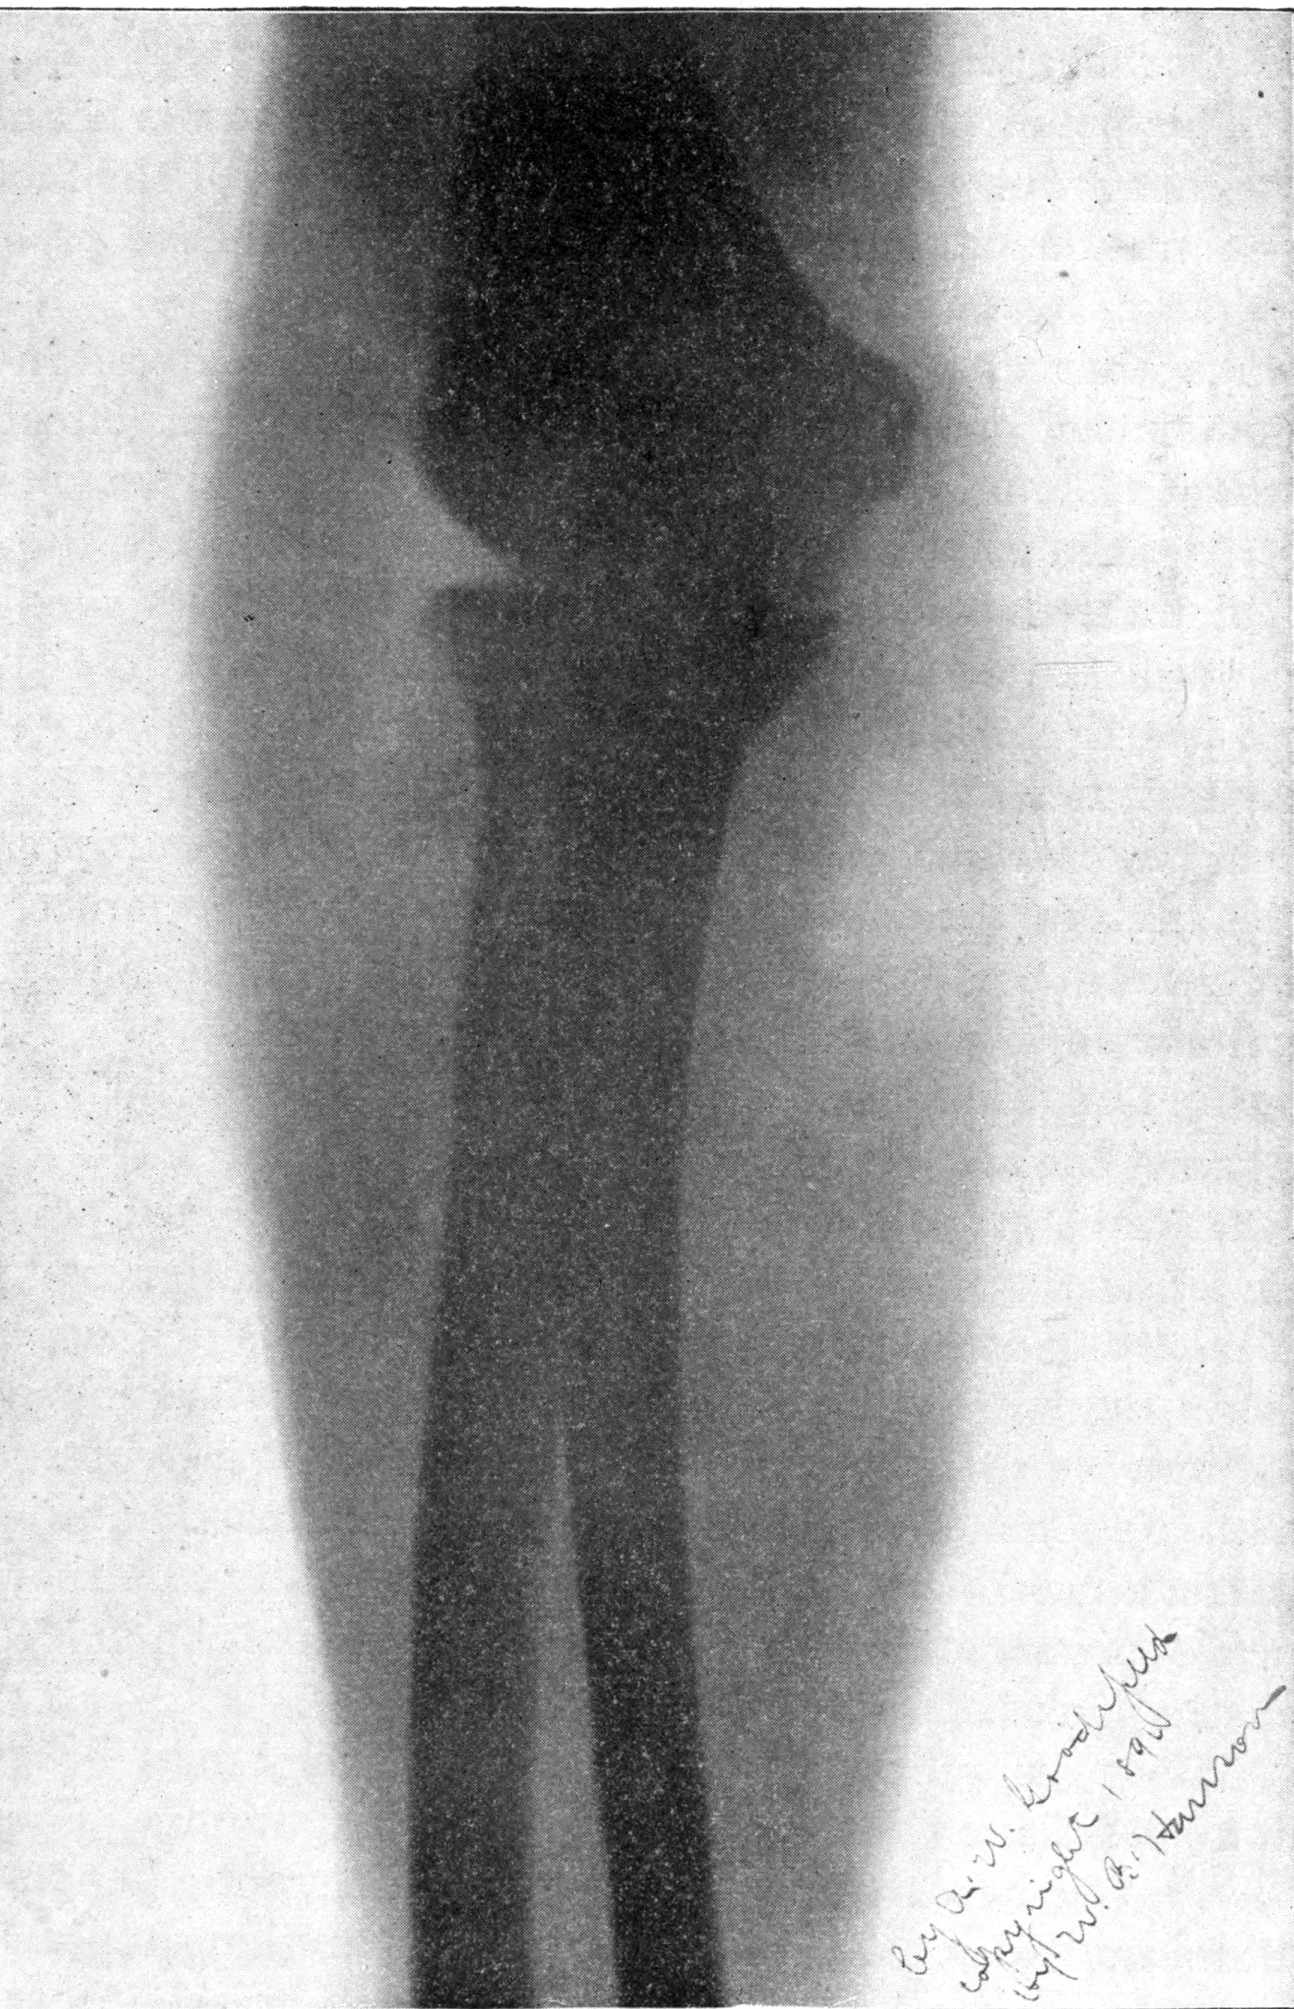

Fig. 2.—Broken Arm, Overlapping.

(Due to defective setting.)

Fig. 4.—Knee, Knickerbocker Buttons, Bullet in Femur.

FROM SCIAGRAPHS BY PROF. DAYTON C. MILLER. § 204.